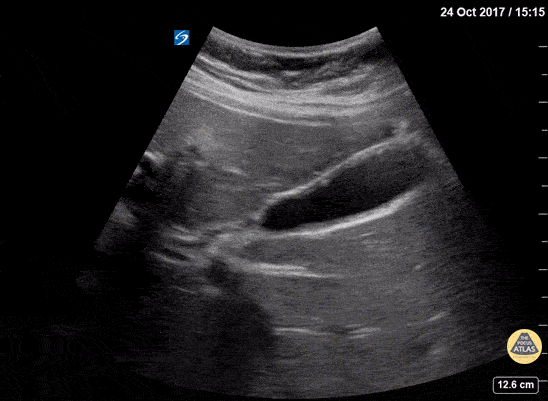

Biliary - Adenomyomatosis

Adenomyomatosis is a generally benign condition characterized by diffuse thickening of the gallbladder wall and intramural diverticula. On ultrasound it creates comet tail artifacts (reverberation artifacts that appear as tiny echogenic beams) originating from distinct locations on the gallbladder wall. This is often seen in asymptomatic patients; however it can be associated with chronic inflammation from gallstones and pancreatitis. Dr. Lindsay Davis - NYU/Bellevue Department of Emergency Medicine